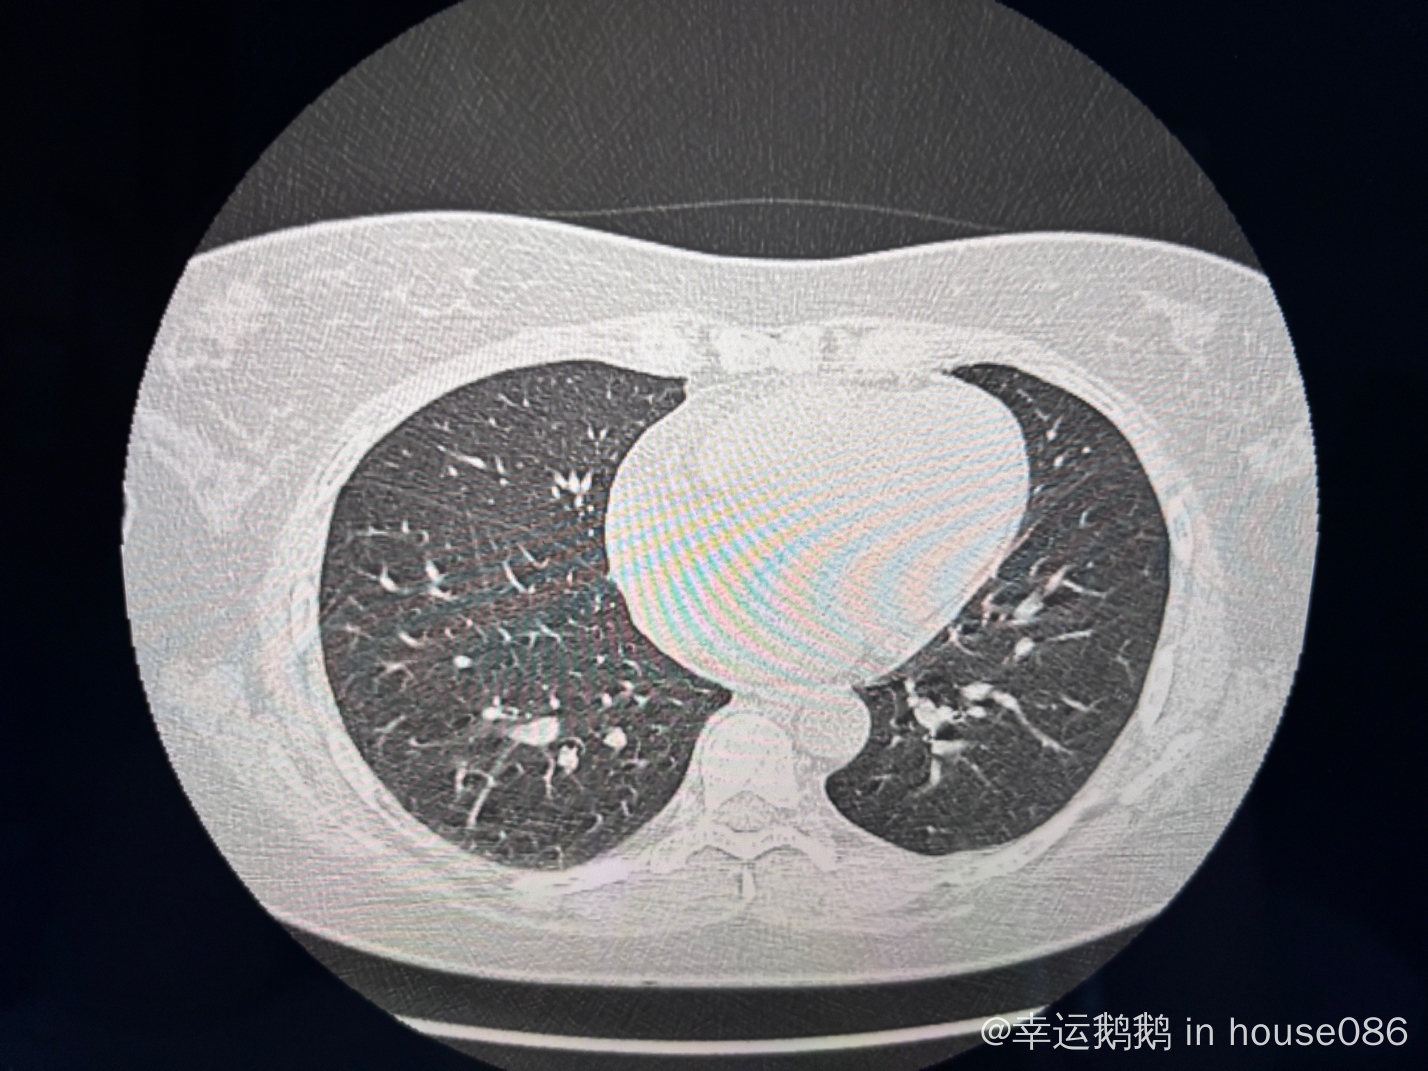

上午刚做的petCT, 还没出报告,请问这个肺像是间质性肺炎吗?

请问下各位大佬这个肺是不是像间质性肺炎表现? 万分感谢!

之前我见过其他人的图像,典型特征是那种蜂窝状、毛玻璃样的阴影,只能说你发的这个图像看着不太像,我觉得还要结合一些症状,比如咳嗽,呼吸气短啥的,还是尽快跟医生联系综合的看一下比较妥